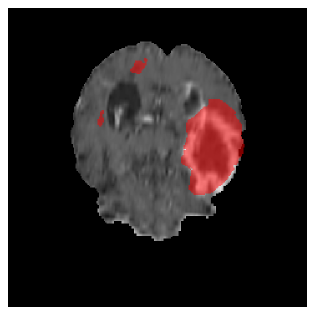

Appendix A Qualitative results

Figures 4 and 5 present the segmentation results for a patient from the BRATS dataset, visualized on a randomly selected slice. Figure 4 illustrates how tumor segmentation evolves over multiple episodes in S1 across different approaches including cumulative, naive, our approach, and the best buffer-free strategy (SI, =2). The cumulative approach, which trains on all encountered datasets together, maintains segmentation consistency across episodes but introduces significant amounts of false positives, particularly in the upper left area of the brain images. These misclassifications highlight its inability to generalize well across datasets despite access to all previous data. The naive approach, which learns sequentially without any continual learning strategy, suffers from severe catastrophic forgetting. While it initially segments well, performance deteriorates over episodes, leading to a near-complete loss of segmentation capability by the final episode. The SI (=2) approach, a regularization-based buffer-free CL strategy, performs reasonably well in early episodes but shows a significant performance decline over time. By the last episode, much of the tumor was no longer segmented, indicating difficulty in retaining prior knowledge. In contrast, our proposed approach initially produces more false positives but progressively refines its segmentation. By the final episode, it accurately retains the tumor region while minimizing misclassifications, demonstrating strong knowledge retention and adaptability across episodes. This suggests that our approach effectively mitigates catastrophic forgetting while maintaining segmentation performance over sequential learning.